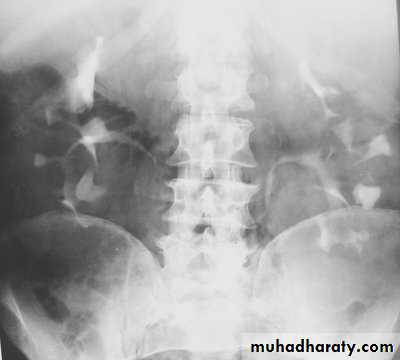

Poly cystic disease

Adult typePresent after the third decade of life , Familial.

Renal parenchyma is replaced by numerous cysts containing fluid , The cysts are of variable size ,

Clinically renal colic, loin mass , heamaturia and hypertension, Renal tissue interposed between the cysts after time dssimcted ended with renal failure

Almost bilateral.

IVU

Large kidney .Lobulated out-line.

Distortion of pelvi- calyceal system depend on cyst size, number and position.

In advanced cases there is elongation and stretching of minor and major calyces ( spider leg).

In advanced cases IVU shows non-functioning kidney .